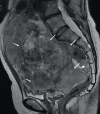

Although rare, uterine sarcoma is a diagnosis that no one wants to miss. Often benign leiomyomas (fibroids) and uterine sarcomas can be differentiated due to the typical low T2 signal intensity contents and well-defined appearances of benign leiomyomas compared to the suspicious appearances of sarcomas presenting as large uterine masses with irregular outlines and intermediate T2 signal intensity together with possible features of secondary spread. The problem is when these benign lesions are atypical causing suspicious imaging features. This article provides a review of the current literature on imaging features of atypical fibroids and uterine sarcomas with an aide-memoire BET1T2ER Check! to help identify key features more suggestive of a uterine sarcoma.